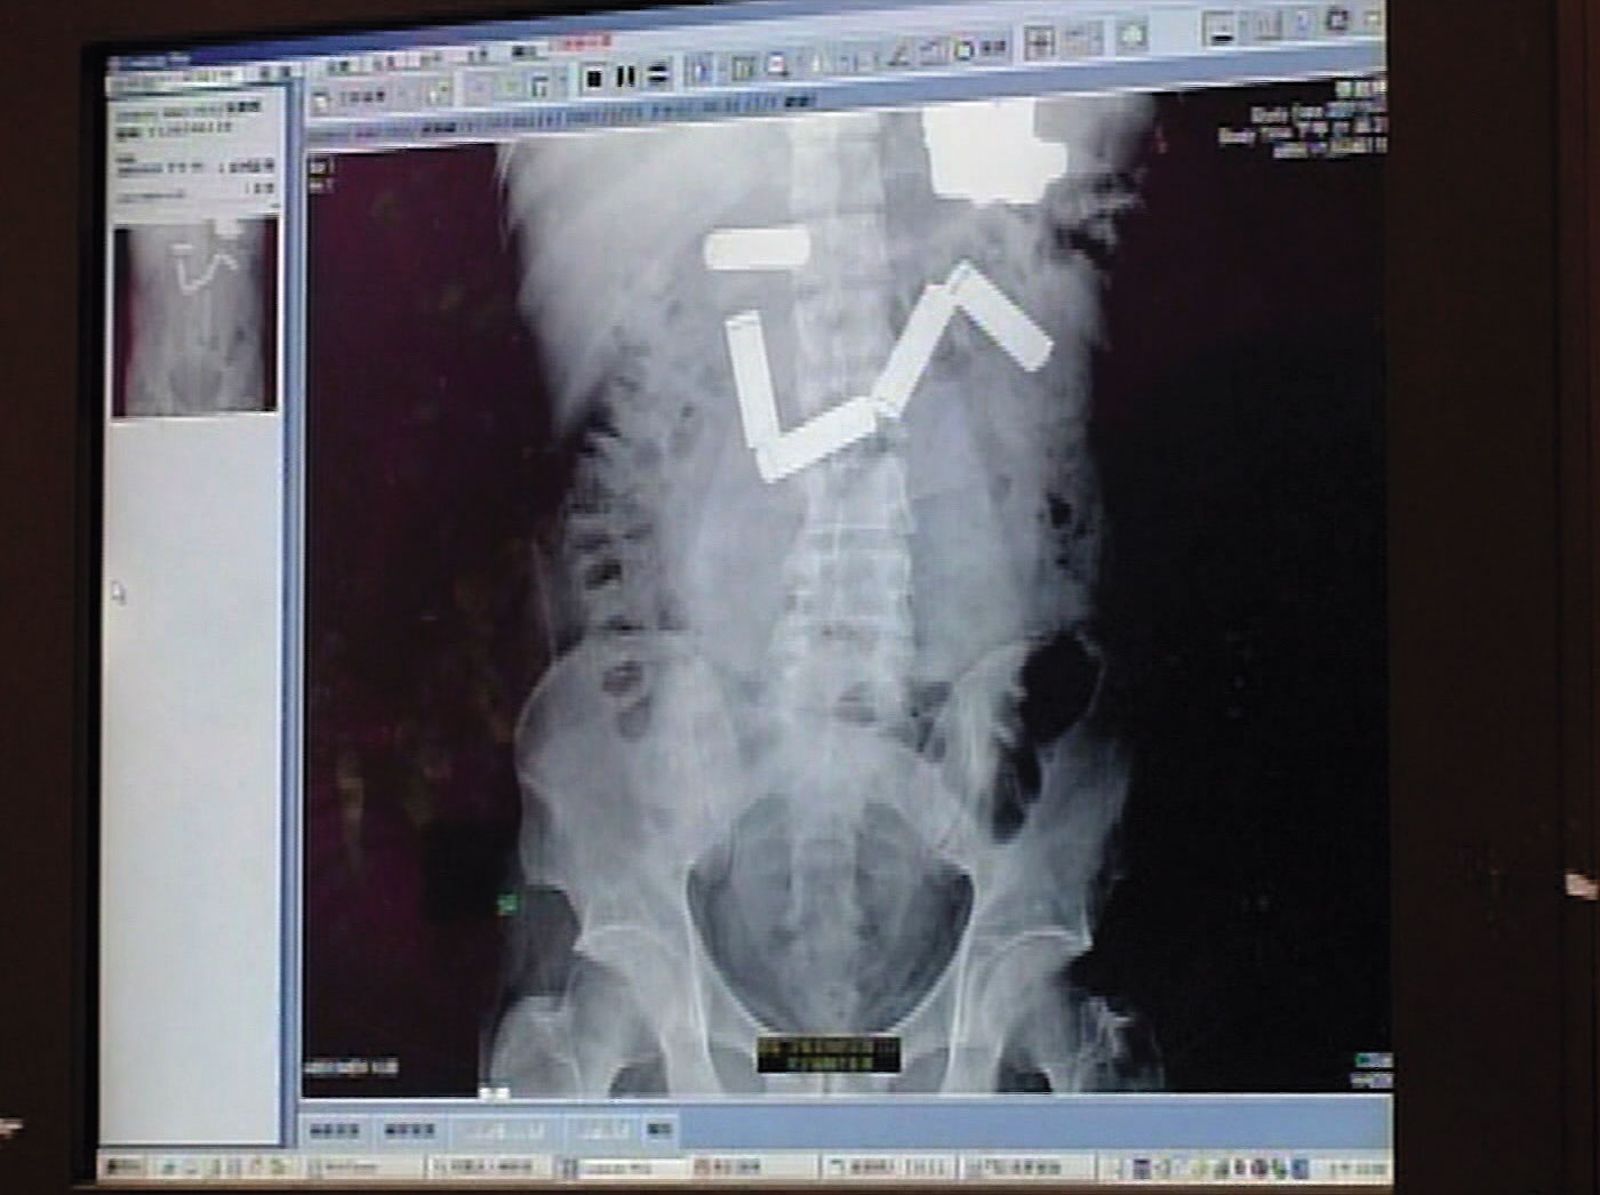

針對雙方論戰,歷審法院都認同檢方見解,認定張胞輝殺害2名鄰居時,不符精神耗弱減刑要件,判張死刑,2005年,最高法院駁回張的上訴,判決他死刑定讞,沒想到他在等待執行期間,又吞下多顆電池企圖自殺,送醫急救開刀後,保住性命。一直到死刑定讞8年之後,張才終於槍決伏法,為背負的3條人命付出代價。

張胞輝等待槍決期間,在看守所吞電池自殺,送醫開刀後撿回一命。(東森新聞提供)